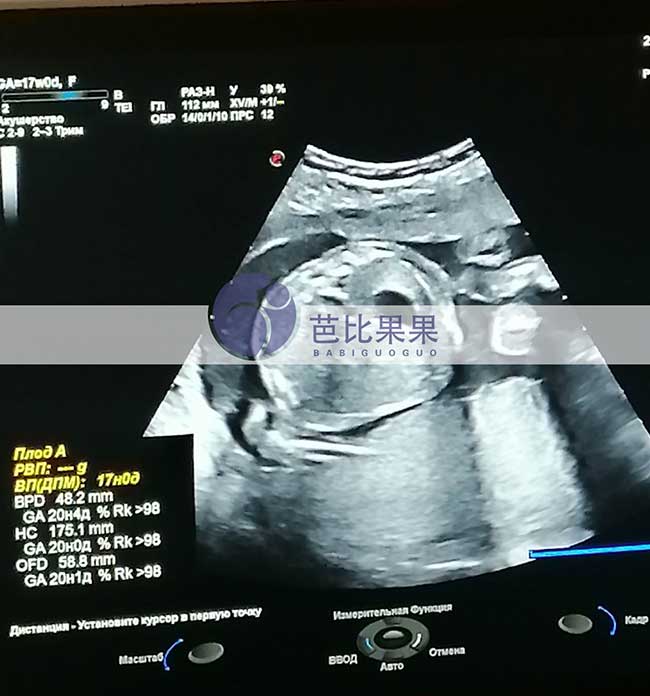

J先生的乌克兰试管妈妈按时基辅妇产医院做孕17周B超孕检

J先生家乌克兰试管妈妈按时到我们熟悉的基辅妇产医院做孕17周B超孕检,胎儿发育得很好,孕妈身体状态也很好,辛苦她了